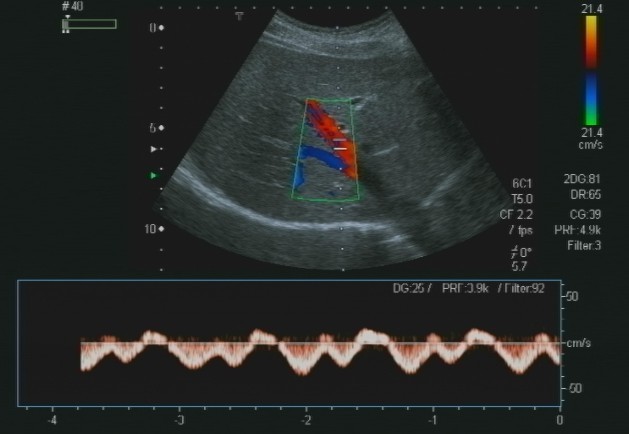

Lo studio medico privato del Dottor Patrizio Stornelli è ad Avezzano è dotato di un'attrezzatura ecografica moderna. Oltre alla ecografia addominale dei parenchimi, si esegue l'ecografia gastroenterolgica ed in particolare l'ecografia del tenue, che consente la diagnosi ed il follow-up particolaremente dei paziente con malattia di Crohn, ma anche l'ecografia del colon. Grazie a questo approccio è possibile scansionare interi segmenti del colon con particolare riguardo alla patologia diverticolare ma anche di indiduare l'appendice e di porre diagnosi di certezza di eventuale appendicite acuta.